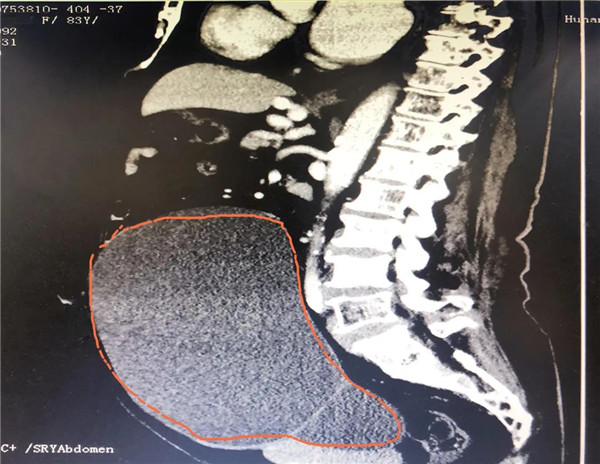

CT显示,巨大的肿瘤几乎占据老人整个盆腔和腹腔。

2021年10月29日,彭娭毑住进湖南省人民医院妇科病房。完善相关检查发现,巨大的肿瘤几乎占据她整个盆腔和腹腔,并且压迫肠道和膀胱,这也是老人尿频的原因。与此同时,术前血液检查发现了异常——全系细胞减少;进一步骨髓穿刺结果为:可疑B细胞淋巴瘤骨髓浸润。

经过充分讨论并做好充足的术前准备后,11月12日,妇科黄薇主任团队在麻醉科、手术室的配合下,秉持无瘤操作原则,为老人施行单孔腹腔镜手术。在肚脐上打一个小孔,缓慢引流出约4000毫升清亮的囊液。术中发现,左侧巨大的卵巢肿瘤与肠管致密大片粘连。精细分离后,顺利切除缩小的卵巢肿瘤和双侧附件。快速病检证实为“双侧卵巢浆液性囊腺瘤”。